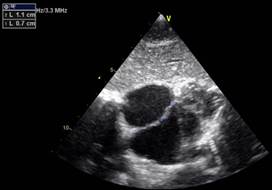

En subcostal 4 cámaras se observa CIA de 7 mm de diámetro con shunt de izquierda a derecha. (Figuras 2,3,4)

Video VIDEOS\CIA TT\CIA ETT.wmv, https://youtu.be/ihgC147F1-s